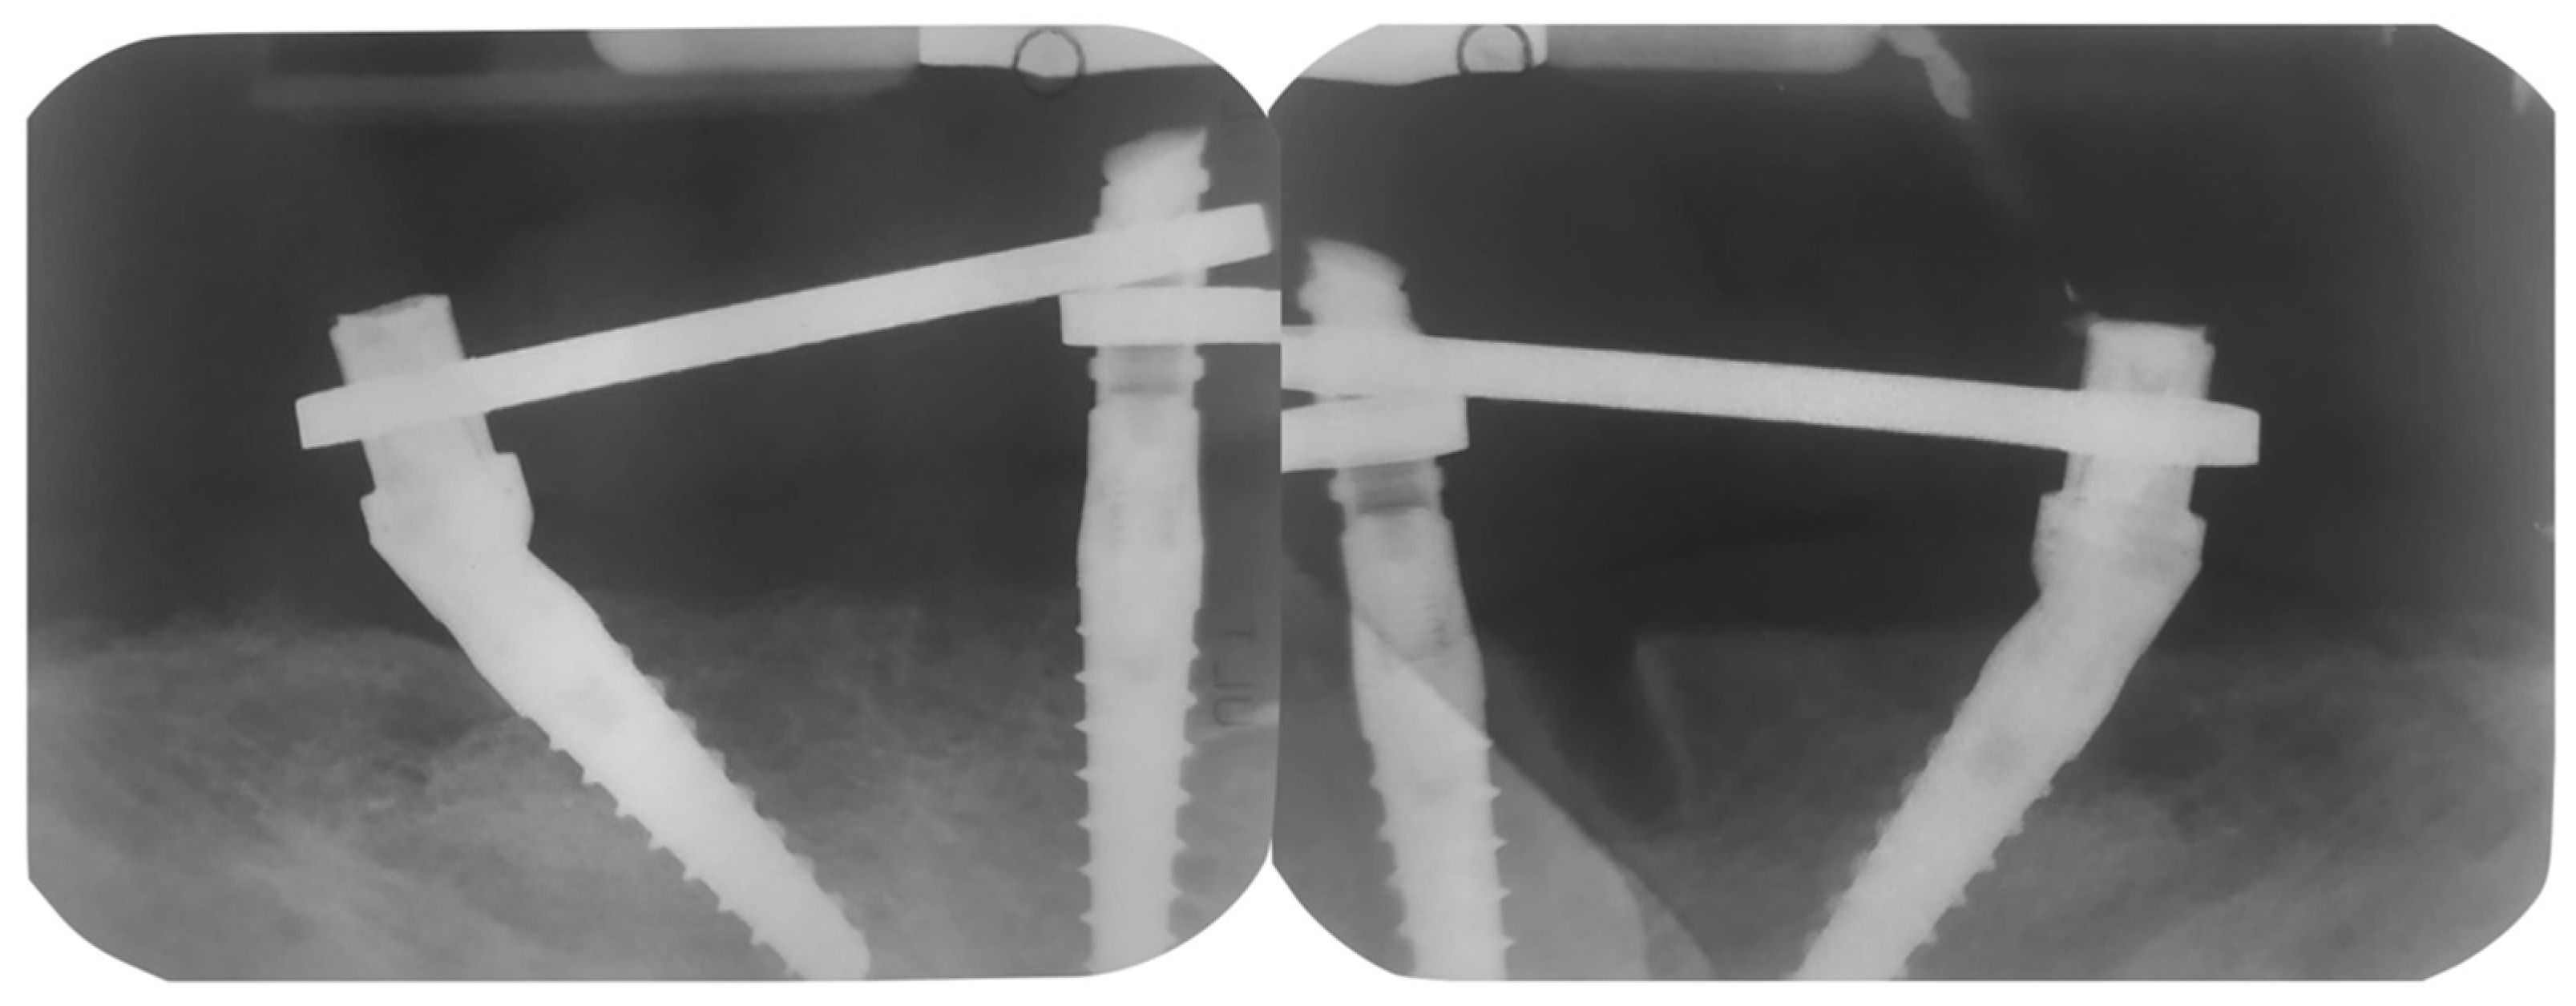

2. Case Report

Surgery Appointment